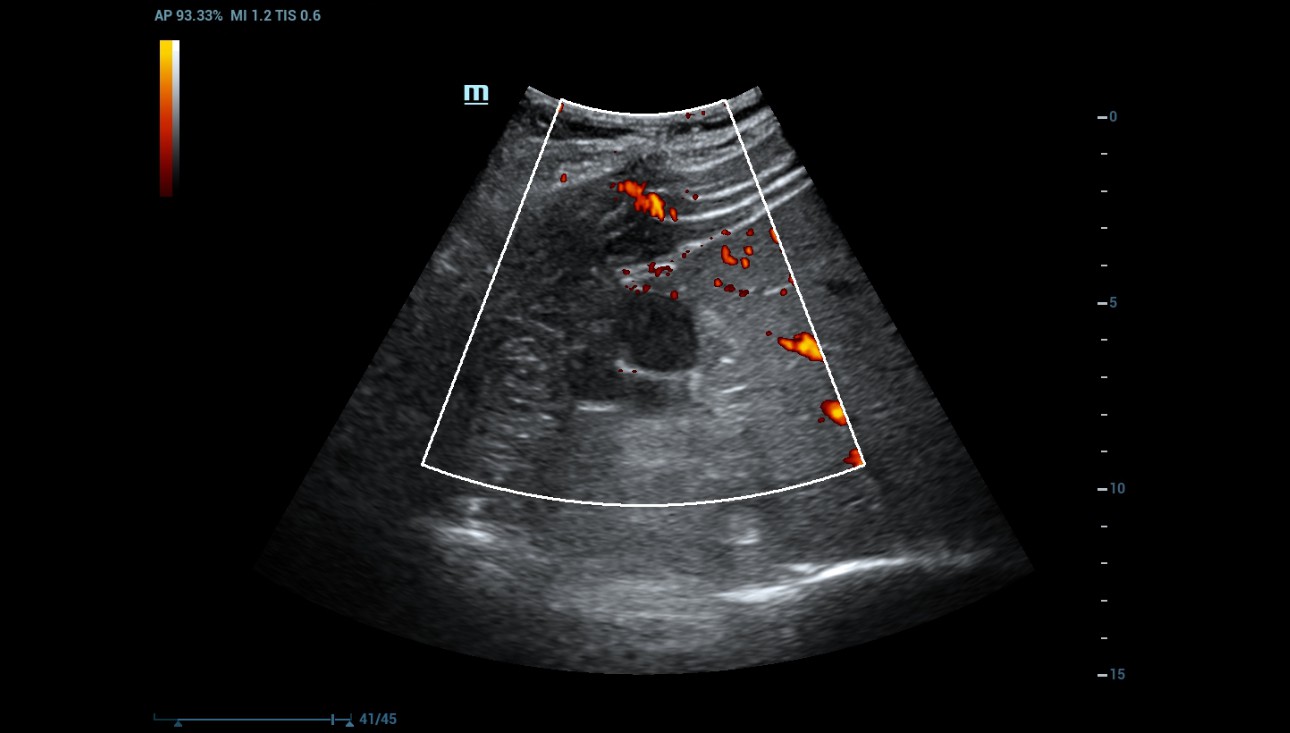

Power Doppler was used to evaluate for internal flow within the complex cystic mass with indeterminate results. (Figure 3).

Figure 3: Power Doppler cannot see any determined internal flow within the complex cystic mass.